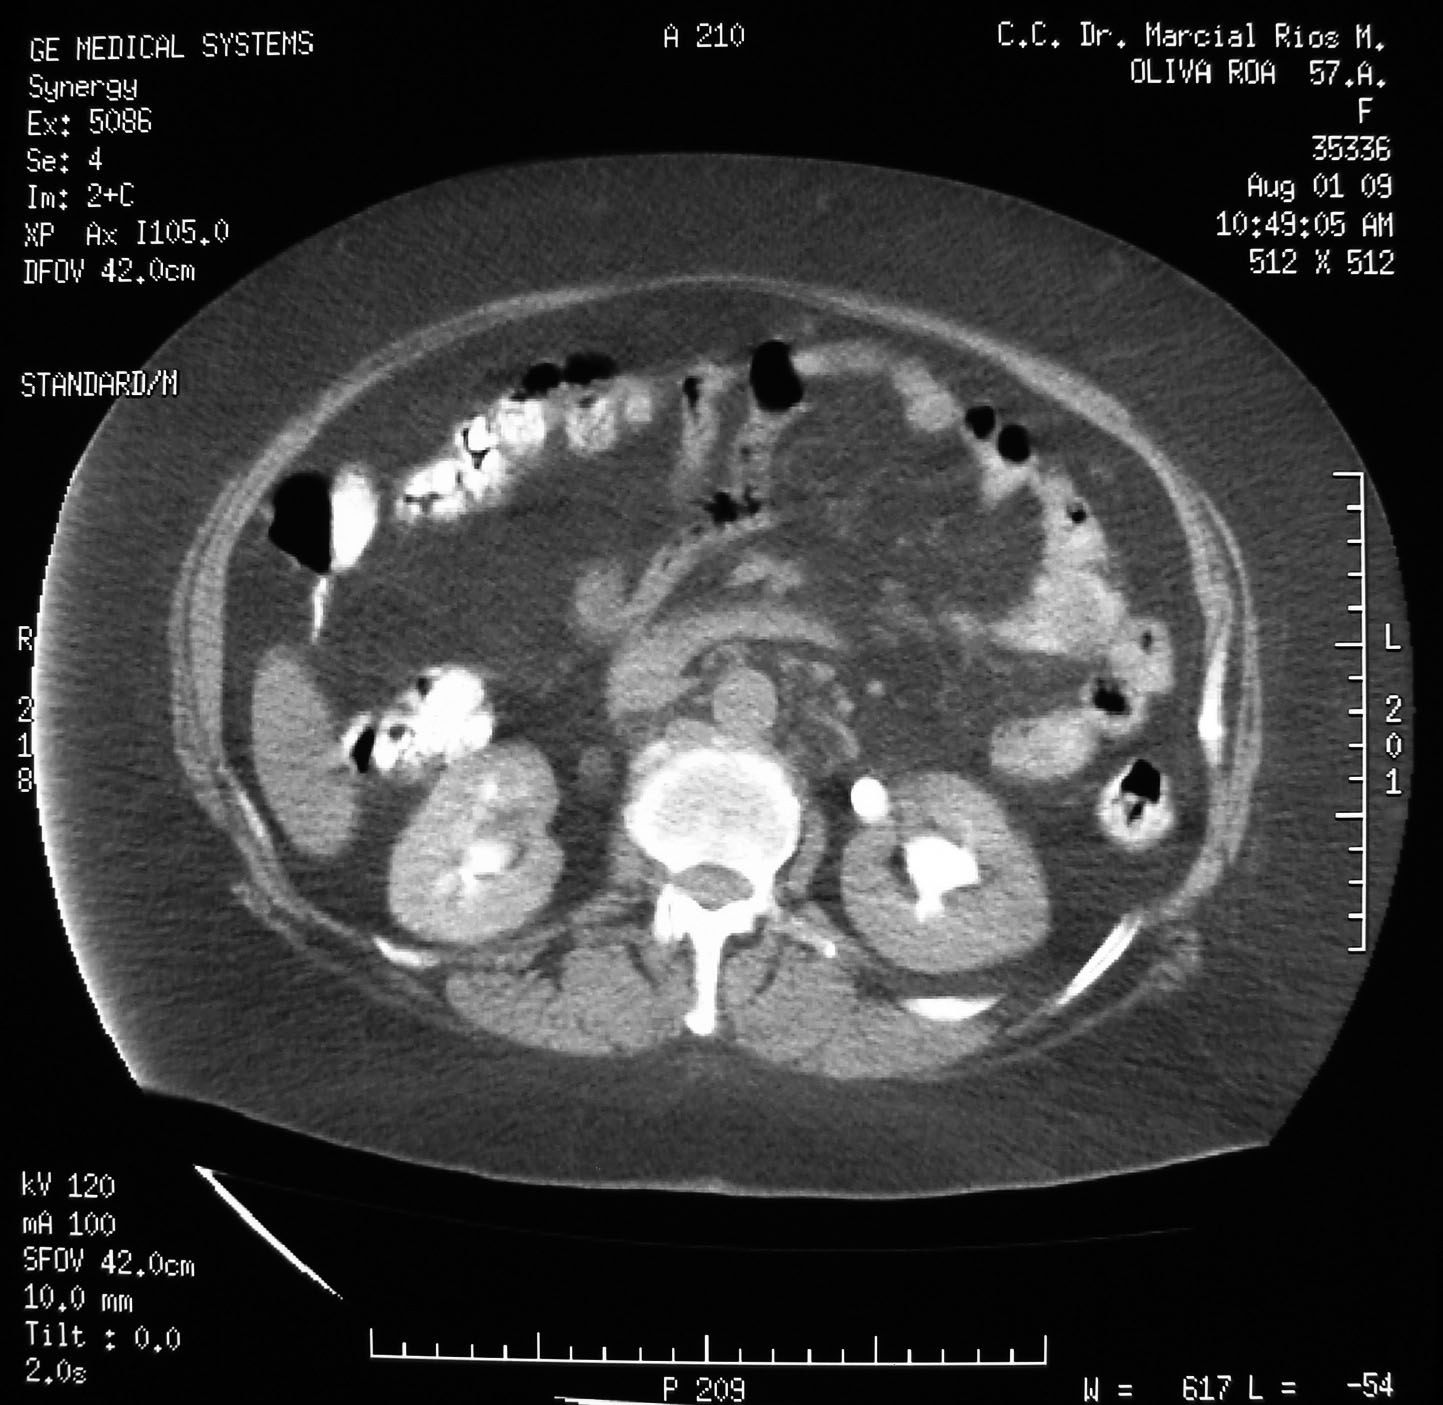

Uterus myomatosus (8)

Hospital Universitario de Los Andes, Dra. Cecilia Perez